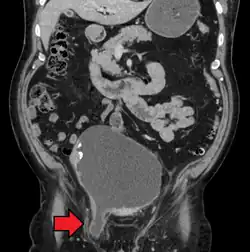

An incarcerated inguinal hernia as seen on cross sectional CT scan

A frontal view of an incarcerated inguinal hernia (on the patient's left side) with dilated loops of bowel above.

An inguinal hernia which contains part of the bladder. Bladder cancer is also present.